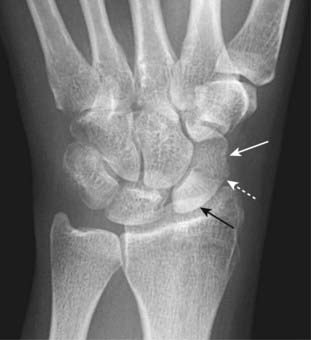

Figure 22-26 Avascular necrosis of the proximal pole of the scaphoid.

A close-up frontal view of the wrist demonstrates that the proximal pole of the scaphoid (solid black arrow) is denser than the distal pole (solid white arrow). There is a fracture through the waist of the scaphoid (dotted white arrow). Because of the peculiar blood supply of the scaphoid (from distal to proximal), fractures through the waist may interrupt the proximal blood supply while the other bones of the wrist, having normal blood supply, become demineralized. This makes the proximal pole of the scaphoid appear denser relative to the other bones of the wrist.